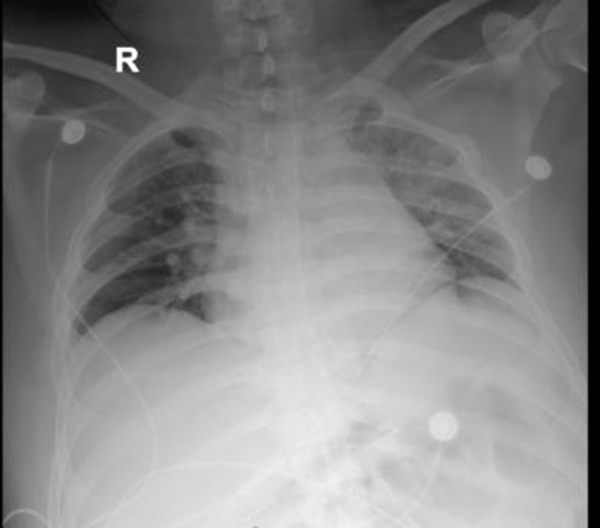

后續(xù)給與積極抗感染等治療,復查胸片示左肺不張改善,體溫正常,炎癥指標下降,再次復查氣管鏡下可見痰量較前明顯減少,總體病情好轉,4月23日轉到普通病房繼續(xù)治療;颊呒覍俦硎,輾轉三家醫(yī)院就醫(yī),還是徐醫(yī)附院最值得信任,對呼吸ICU全體醫(yī)護人員表達了敬意和衷心感謝。